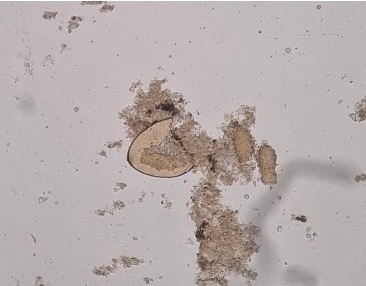

Ovo de Fasciola hepatica